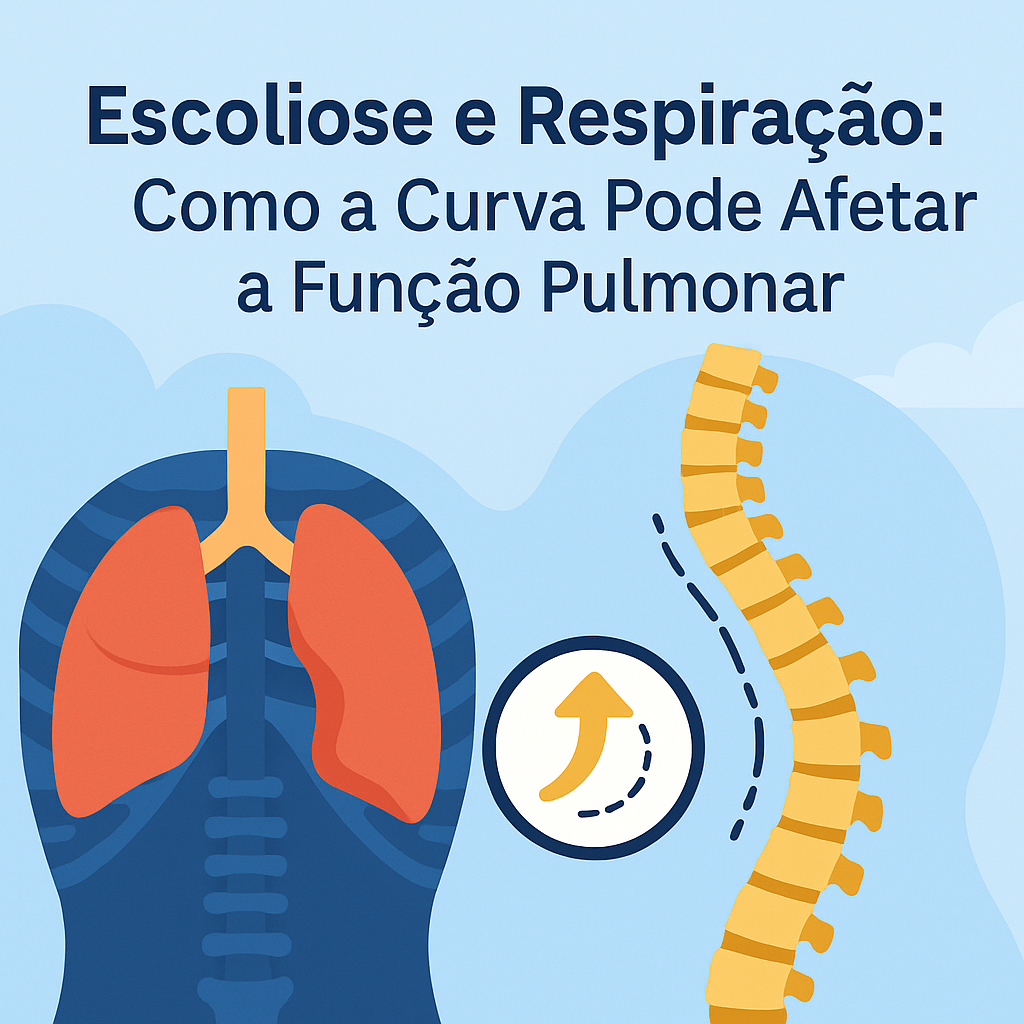

A escoliose torácica pode impactar diretamente a respiração, especialmente quando a curvatura ultrapassa 50–60 graus. A deformidade da coluna altera a anatomia da caixa torácica, reduzindo sua mobilidade e dificultando a expansão pulmonar. Como resultado, pacientes podem apresentar redução da capacidade vital, maior esforço respiratório, cansaço aos pequenos esforços e risco aumentado de infecções pulmonares.

Sinais de alerta incluem: fadiga desproporcional, histórico de infecções respiratórias, hipoxemia noturna e deformidade torácica evidente. A avaliação da função pulmonar deve incluir espirometria e, em casos mais complexos, gasometria, polissonografia e exames de imagem.

O tratamento envolve fisioterapia respiratória, exercícios posturais específicos, ventilação não invasiva quando necessário e, em casos graves, cirurgia corretiva para melhorar a mecânica ventilatória. Monitorar a função respiratória de forma contínua é essencial para prevenir complicações e manter a qualidade de vida.